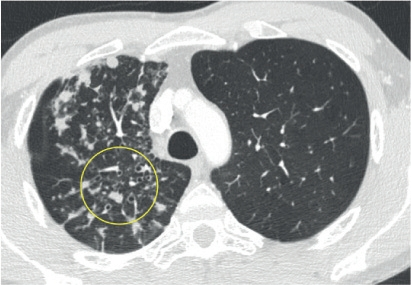

胸部HRCT是首选检查方法,肺结核的CT表现包括小叶中心树芽状影、界限不清的毛玻璃结节、实变区和空洞。肺下叶结核定位通常见于免疫功能低下的患者,并与结核再激活有关,而成人上叶空洞通常是原发感染的特征。

图 结核分枝杆菌感染,右肺上叶CT示多发外周结节及支气管壁增厚